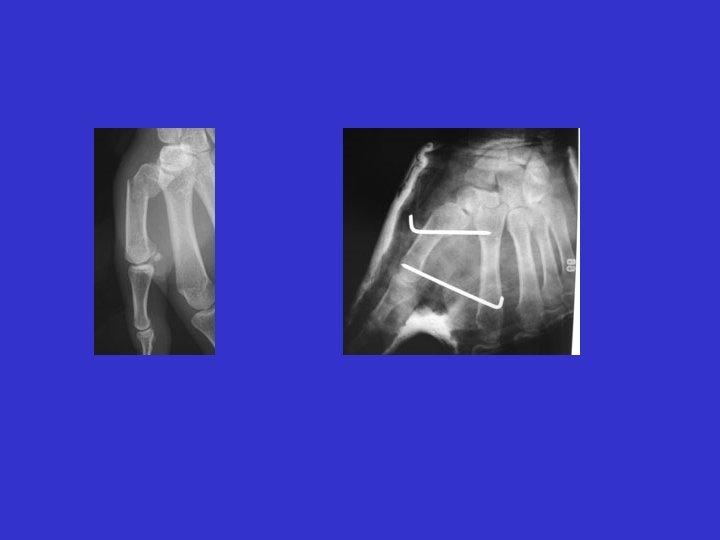

Fracturas de las falanges

Fractura de la primera falange: reducción en flexión

Inmovilización en flexión Técnica de la bola de yeso de Bonvalet

Osteosíntesis de las Falanges

fotos J. Chouteau